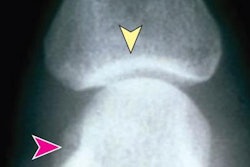

Lateral cervical radiograph with a CT report of fracture at C2 vertebral body and fracture of C3 transverse process. The fractures are not clearly visible on the radiograph (A) and were labeled at the relevant anatomy (B). (C) and (D) are a 3D CT scan of the patient showing fractures at C2 vertebral body and C3 spinous process. Image courtesy of Heliyon.According to the findings, the YOLO-V4 model achieved the highest sensitivity of the three models, at 80%, as well as a specificity of 72% and an accuracy of 80% for detecting spine injury. Compared with the radiology resident, the model had a higher accuracy (p = 0.012) and specificity (p = 0.011), but there was not a statistically significant difference between the model and the radiologist or the orthopedist, the authors wrote.